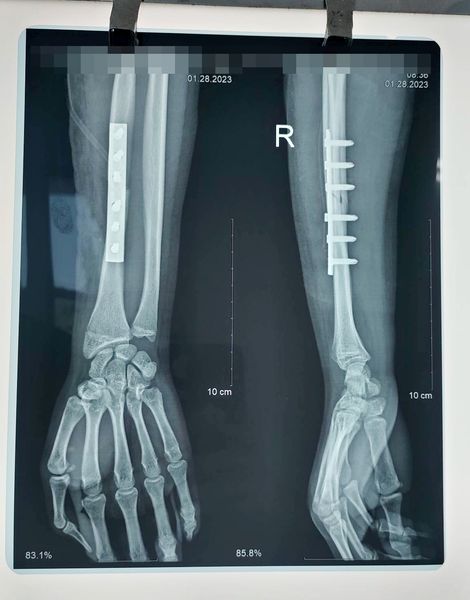

Hoàn thành ca phẫu thuật xương cho bệnh nhân 17 tuổi gãy giữa xương quay phải do tai nạn giao thông.

Sau khi phẫu thuật bệnh nhân đã ổn định và dự kiến sau 7 ngày có thể ra viện.